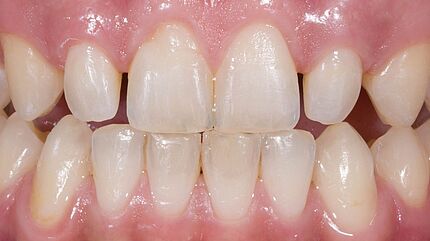

Ein eindrücklicher Case Report ist in der Quintessenz Zahnmedizin publiziert: Der Erhalt der ursprünglichen Gewebearchitektur in der ästhetischen Zone ist eine zentrale Herausforderung in der modernen, zahnärztlichen Implantologie. Wenn die Voraussetzungen für eine Sofortimplantation mit einer prothetischen Sofortversorgung gegeben sind, ist dies ein möglicher Weg die ursprüngliche Morphologie der Hart- und Weichgewebe weitgehend zu erhalten. Der vorliegende Beitrag definiert die Begriffe Sofortimplantation, Sofortversorgung sowie Sofortbelastung und illustriert einen klinischen Fall bei dem nach Fraktur eines Frontzahnes eine Sofortimplantation mit provisorischen Sofortversorgung realisiert werden konnte.

Zeitschrift: Quintessenz Zahnmedizin

Ausgabe: 11/2022, S. 1028 - 1036

Autoren: Dr. Christopher Prechtl, PD Dr. Daniel Hellmann, Dr. Dr. Hans Ulrich Brauer, M.A., M.Sc.